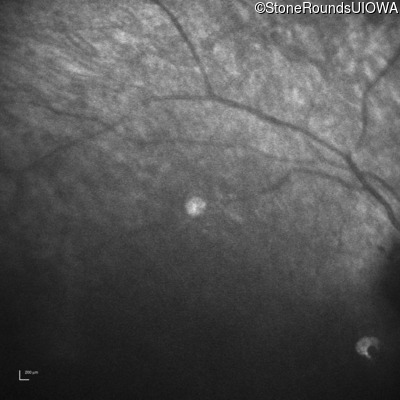

Infrared Fundus Photograph - Right -

No Light Perception

Exemplar

Expanded OCT Stack

×